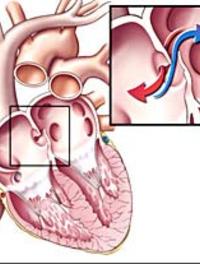

Soupçonné depuis la fin du 19ème siècle, le rôle de la persistance d’un foramen ovale perméable (patent foramen ovale [PFO]) dans l’étiologie [...]